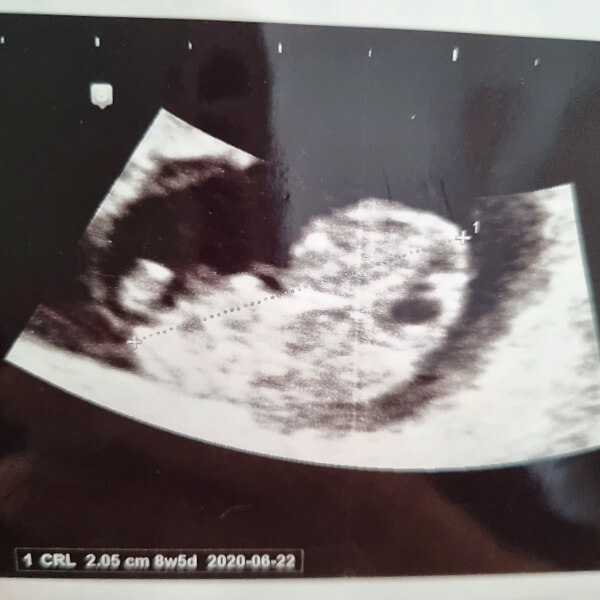

2. 초음파 계산법

마지막 생리일이 정확하지 않거나 생리주기가 불규칙하다면 초음파 검사로 계산하는 방법도 있습니다. 일반적으로 정기검진을 받을 때 의사 선생님께서 출산예정일 계산할 때 사용하는 방법입니다. 초음파로 태아의 머리에서 엉덩이까지의 길이를 재고 개월 수는 산출하는 방법으로 다른 방법보다 정확하다는 장점이 있습니다.